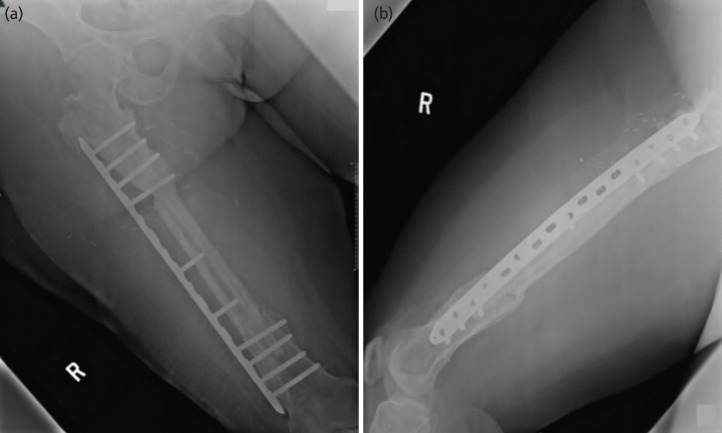

Surgical management of femur osteomyelitis remains challenging. The burden of this chronic disease invariably results in composite bony and soft tissue defects that can interfere with bony stability. Therefore, reconstructive surgery is integral to functional limb salvage and limb preservatives. To the best of our knowledge, we are the first to report the limb salvaging method and important planning considerations for a case of chronic refractory osteomyelitis. We presented a case of a 31-year-old female with chronic post-traumatic osteomyelitis of the right femur. This intractable disease results in frequent remission of infection and non-union of the midshaft fracture. Surgical management with the implant, external fixation, and cement spacer failed due to infection. This rendered vascularised bone graft with massive allograft the only option. We described the anatomical aberrant during the harvest of free fibula flap and modified chimeric fibula flap to overcome the soft tissue defect complicated with severe fibrotic tissue with a background of an obese patient. She had undergone emergency hematoma evacuation 20 hours after the surgery. Otherwise, the flap survived well, and the patient started to have partial weight bearing. Chimeric fibula osteocutaneous free flap is a useful armament to provide a complex 3-dimensional spatial arrangement in a case of chronic osteomyelitis with huge bony and soft tissue defects.